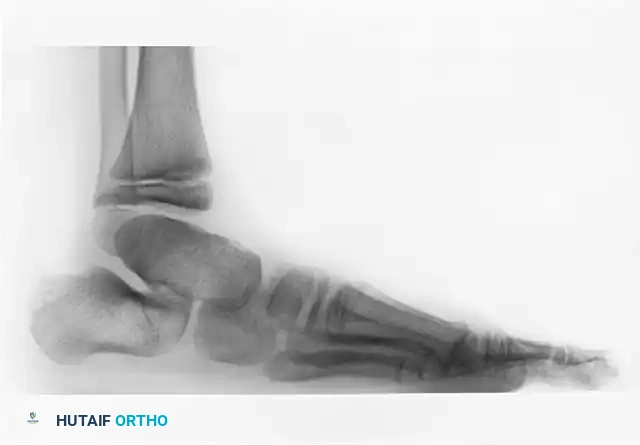

FIGURE 82-76 B: Congenital talonavicular tarsal coalition (Lateral view).